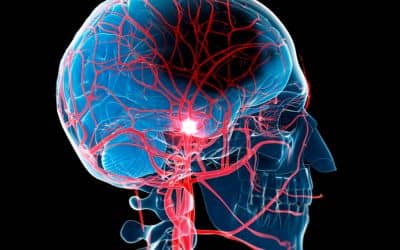

La Medicina Física y Rehabilitación es la especialidad médica a la que concierne el diagnóstico, evaluación, prevención y tratamiento de la discapacidad encaminados a facilitar, manetener o devolver el mayor grado de capacidad funcional e independencia posible.